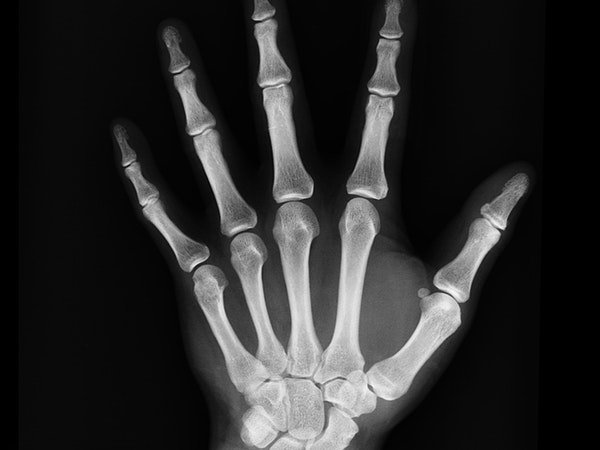

గౌట్ అనేది మీ శరీర కీళ్ళ భాగాలైన బొటనవేలు, చీలమండలు, మోకాలు, మోచేతులు, మణికట్లు & చేతి వేళ్లలో యూరిక్ యాసిడ్ క్రిస్టల్ నిక్షేపణ వలన కలిగే ఒక బాధాకరమైన పరిస్థితి. చెర్రీస్లో ఉండే యాంతోసైనిన్లు మీ రక్తంలో గల యూరిక్ యాసిడ్ క్రిస్టల్ స్థాయిలను తగ్గించడంలో బాగా సహాయపడుతుంది. ఈ చెర్రీస్ను ఎక్కువగా తినడం వల్ల గౌట్ సంబంధిత నొప్పులను, వాపులను తగ్గించగలిగే ఒక గొప్ప మార్గం.